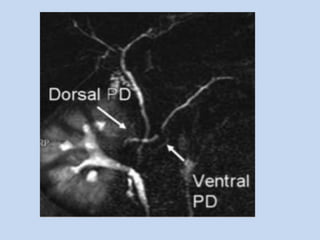

• In pancreatic divisum :

- occurs in 5.5 – 7.5% individuals

- MC variant of pancreatic duct, where the dorsal &

ventral anlage of the pancreas fail to fuse – resulting

in two separate drainage routes for pancreatic

secretions.

APPLICATIONS • In pancreaticdivisum : - occurs in 5.5 – 7.5% individuals - MC variant of pancreatic duct, where the dorsal & ventral anlage of the pancreas fail to fuse – resulting in two separate drainage routes for pancreatic secretions.